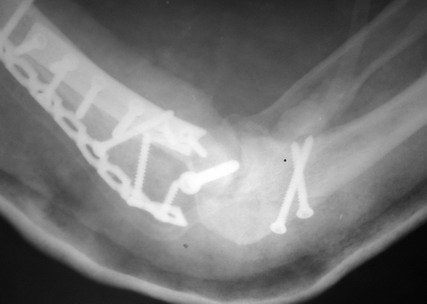

Солидарен с мнением обоих Александров (Челнокова и Рыкова): точную репозицию такого перелома вряд ли удастся выполнить закрыто. Даже во время открытого вмешательства это сделать непросто. Неслучайно предложен костно-пластический доступ с временным отсечением локтевого отростка. И по методу фиксации согласен с Александром Челноковым: 2 пластины. В качестве примера привожу рентгенограммы одного из наших пациентов с аналогичным повреждением.

С уважением, А. Золотов, Приморский край.